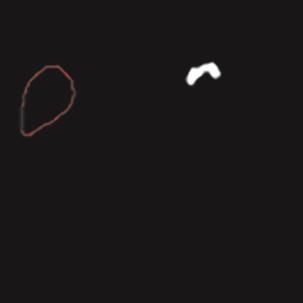

乳腺癌是全球女性最常见的恶性肿瘤之一,准确的病变分割对于乳腺癌的早期诊断与治疗具有重要意义。然而,由于病变形态的多样性以及超声成像机制的复杂性,现有基于深度学习的乳腺超声图像病变分割方法在分割准确性方面仍面临巨大挑战。为进一步提升乳腺超声图像中病变区域的分割精度,该文基于经典U-Net架构,提出了一种新型乳腺超声图像病变分割网络(CWSASKM-BBAM-Net)。首先,在网络中引入逐通道空间自适应选择核卷积模块(CWSASKM),根据不同通道的语义特征为每个空间位置自适应选择感受野大小,以增强多尺度信息的建模能力;然后,引入双向边界感知机制(BBAM),通过融合正向与反向注意力,对目标显著区域及其边界进行协同建模,同时逐步提升对非显著区域与病变区域的区分能力,以进一步强化边界信息的表达;最后,在3组公开乳腺超声图像数据集(BUSI、UDIAT和STU)上开展分割实验。结果表明:该方法在数据集BUSI上的杰卡德指数、精确率、召回率和Dice相似系数分别为71.97%、82.85%、81.40%和80.44%,较次优方法分别提升1.69、1.05、1.28和1.84个百分点;在数据集UDIAT上,这4项指标分别达到78.14%、88.31%、86.73%和86.10%,较次优方法分别提升了2.75、2.04、0.56和2.01个百分点;在外部数据集STU上,该方法也取得了优于其他方法的整体表现。实验结果表明,CWSASKM-BBAM-Net在乳腺超声图像分割任务中展现出更优的整体性能。